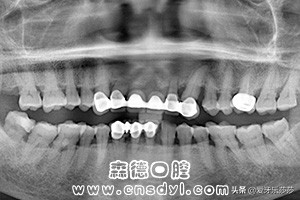

首先呢,是烤瓷冠的数量~

大家都知道,烤瓷冠大都无法过多受力,而当口腔内烤瓷冠的数量较多时,是会影响正常矫正的加力。若只有一两颗烤瓷冠,是可以通过主治医师的检查评估后确定。但当你的牙齿过于拥挤需要拔牙时候,主治医师会在给你设计矫正方案时优先考虑拔除烤瓷冠的。

其次呢,是烤瓷冠位置~

嗯~一般情况来讲,牙齿矫正期间第二磨牙是基本无需上托槽,因此当烤瓷冠是处于这个位置,而且比较正无需移动时,则是不会影响牙齿矫正。但是呢~如果你的烤瓷冠是门牙的话就会有比较大的影响了。因为门牙在牙齿矫正里是需要直接受力的,而且烤瓷牙表面十分光滑,托槽、附件啊都是难以粘牢的。

最后呢,是烤瓷冠的类型~

一般我们做的烤瓷冠大都分为单冠和连冠,连冠的烤瓷冠是无法单颗移动,会直接影响矫正效果。因此当小伙伴戴的是搭桥连冠烤瓷冠的话,则需要考虑拆除,等矫正牙齿后完成后再重新制作。若连冠烤瓷牙涉及到的位置是无需移动呢!,小伙伴则可以选择隐形矫正来移动其他牙齿。